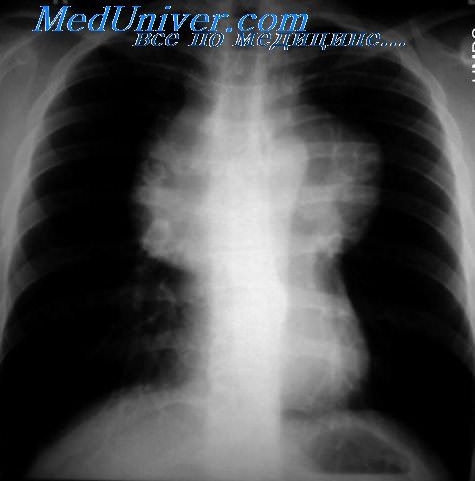

Рентгеновские снимки тератомы средостения: Диагностика и лечение

Раздел: Фотоэссе